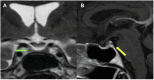

Spontaneous Near-Resolution of a Rathke's Cleft Cyst

Fig. 1